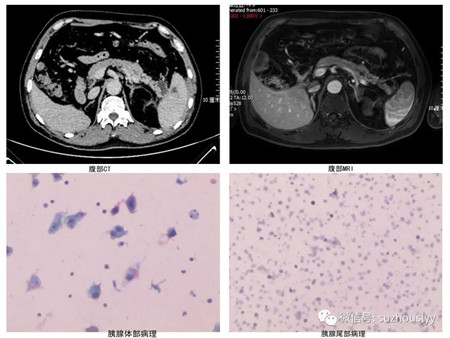

5月7日,我院消化内科在上海瑞金医院王东教授带领下成功开展首例超声内镜引导下胰腺肿物FNA术,标志着我院消化内科超声内镜诊疗技术迈入新台阶。

胰腺占位性病变性质的明确一直是难点,传统影像学如CT、MRI、体表超声等虽是首选检查,但对于鉴别病灶性质作用有限。多年来,超声内镜(EUS)被认为是胰腺和肝外胆道检查最实用的技术,其可以提供胰管及其周围组织的高分辨率图像,在此基础上结合细针穿刺技术(FNA)可以对EUS发现的肿物进行穿刺,迅速获得新鲜标本进行细胞学、组织学检查,EUS-FNA适应症包括:胰腺癌及术前分级、胰腺炎性肿块、胰腺神经内分泌肿瘤、胰腺囊性病变、怀疑慢性胰腺炎、胰腺及胰腺周围大部分区域如胆总管下段和肾上腺、腹膜后淋巴结及占位、后纵隔淋巴结及占位性病变、消化道黏膜下肿瘤或可疑消化道管壁增厚、局灶性肝脏实性占位、直肠周围盆腔占位等。